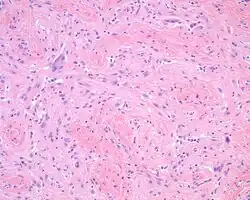

The overlying skin or squamous mucosa is intact and uninvolved by the process. There is normal glial tissue set within a fibrous connective tissue stroma. There is such blending, that the underlying process may be difficult to detect without special studies. In a few cases, large gemistocytes, neurons, choroid plexus, ependyma, and retinal pigmented cells may be seen.[2][3]

Histochemistry

A trichrome stain will highlight the dual components well, with the glial tissue staining red, while the background fibrosis stains a bright blue.[2]